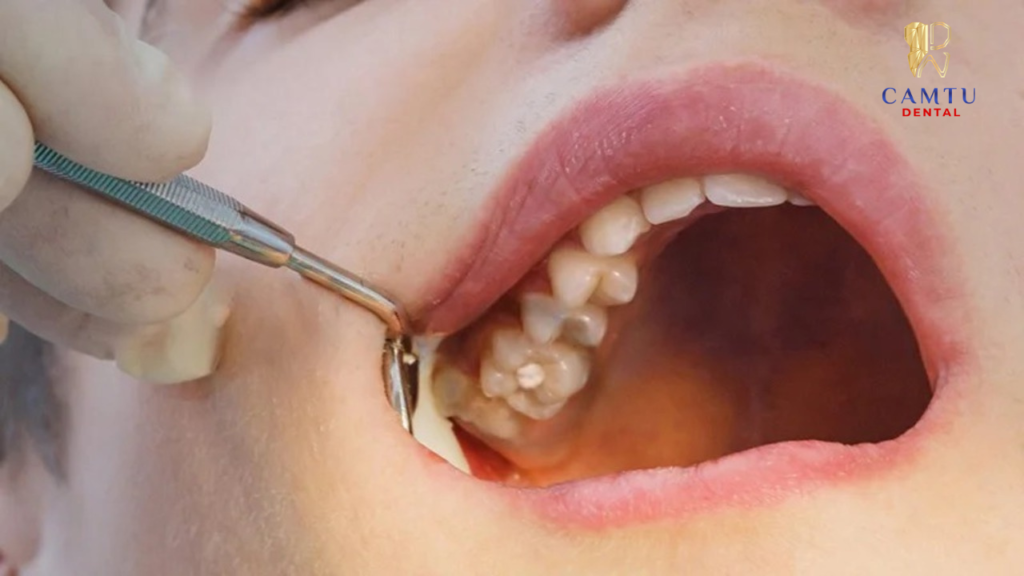

Gây tê và tiến hành nhổ răng

Trước khi nhổ răng, bác sĩ sẽ gây tê cục bộ tại vùng răng cần điều trị để loại bỏ cảm giác đau trong suốt quá trình thực hiện. Khi thuốc tê phát huy tác dụng, bác sĩ sử dụng các dụng cụ nha khoa chuyên dụng để tách răng ra khỏi ổ răng một cách nhẹ nhàng và chính xác.

Quá trình nhổ răng được thực hiện cẩn thận nhằm hạn chế tổn thương đến mô nướu, xương hàm và các răng lân cận. Nhờ vậy, bệnh nhân thường chỉ cảm thấy lực tác động nhẹ thay vì cảm giác đau rõ rệt.